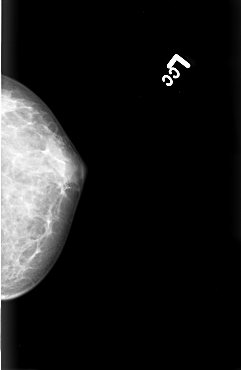

B_3008_1.LEFT_CC

LEFT_CC LINES 4432 PIXELS_PER_LINE 2888 BITS_PER_PIXEL 12 RESOLUTION 50 NON_OVERLAY